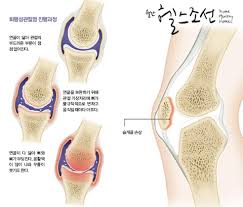

- 관절염: 노화 또는 부상으로 인해 연골이 소실되어 발생하는 관절염은 무릎에 통증을 유발할 수 있습니다.

관절염은 무릎 구부릴 때 통증의 가장 흔한 원인 중 하나입니다. 나이가 들면서 무릎 관절의 연골이 마모되고, 이는 통증과 염증을 유발합니다. 관절염은 퇴행성 변화로 인해 발생하는 경우가 많으며, 일반적으로 노인에게서 더 많이 나타납니다. 관절염으로 인한 통증은 구부릴 때 더욱 심하게 느껴질 수 있으며, 이는 일상적인 활동에 큰 지장을 줄 수 있습니다.

무릎 구부릴 때 통증의 치료 방법은 원인에 따라 달라질 수 있습니다. 일반적으로 사용되는 치료 방법은 다음과 같습니다:

- 물리 치료: 전문 물리 치료사와 함께 운동과 스트레칭을 통해 무릎의 운동 범위를 개선하고 통증을 완화할 수 있습니다.